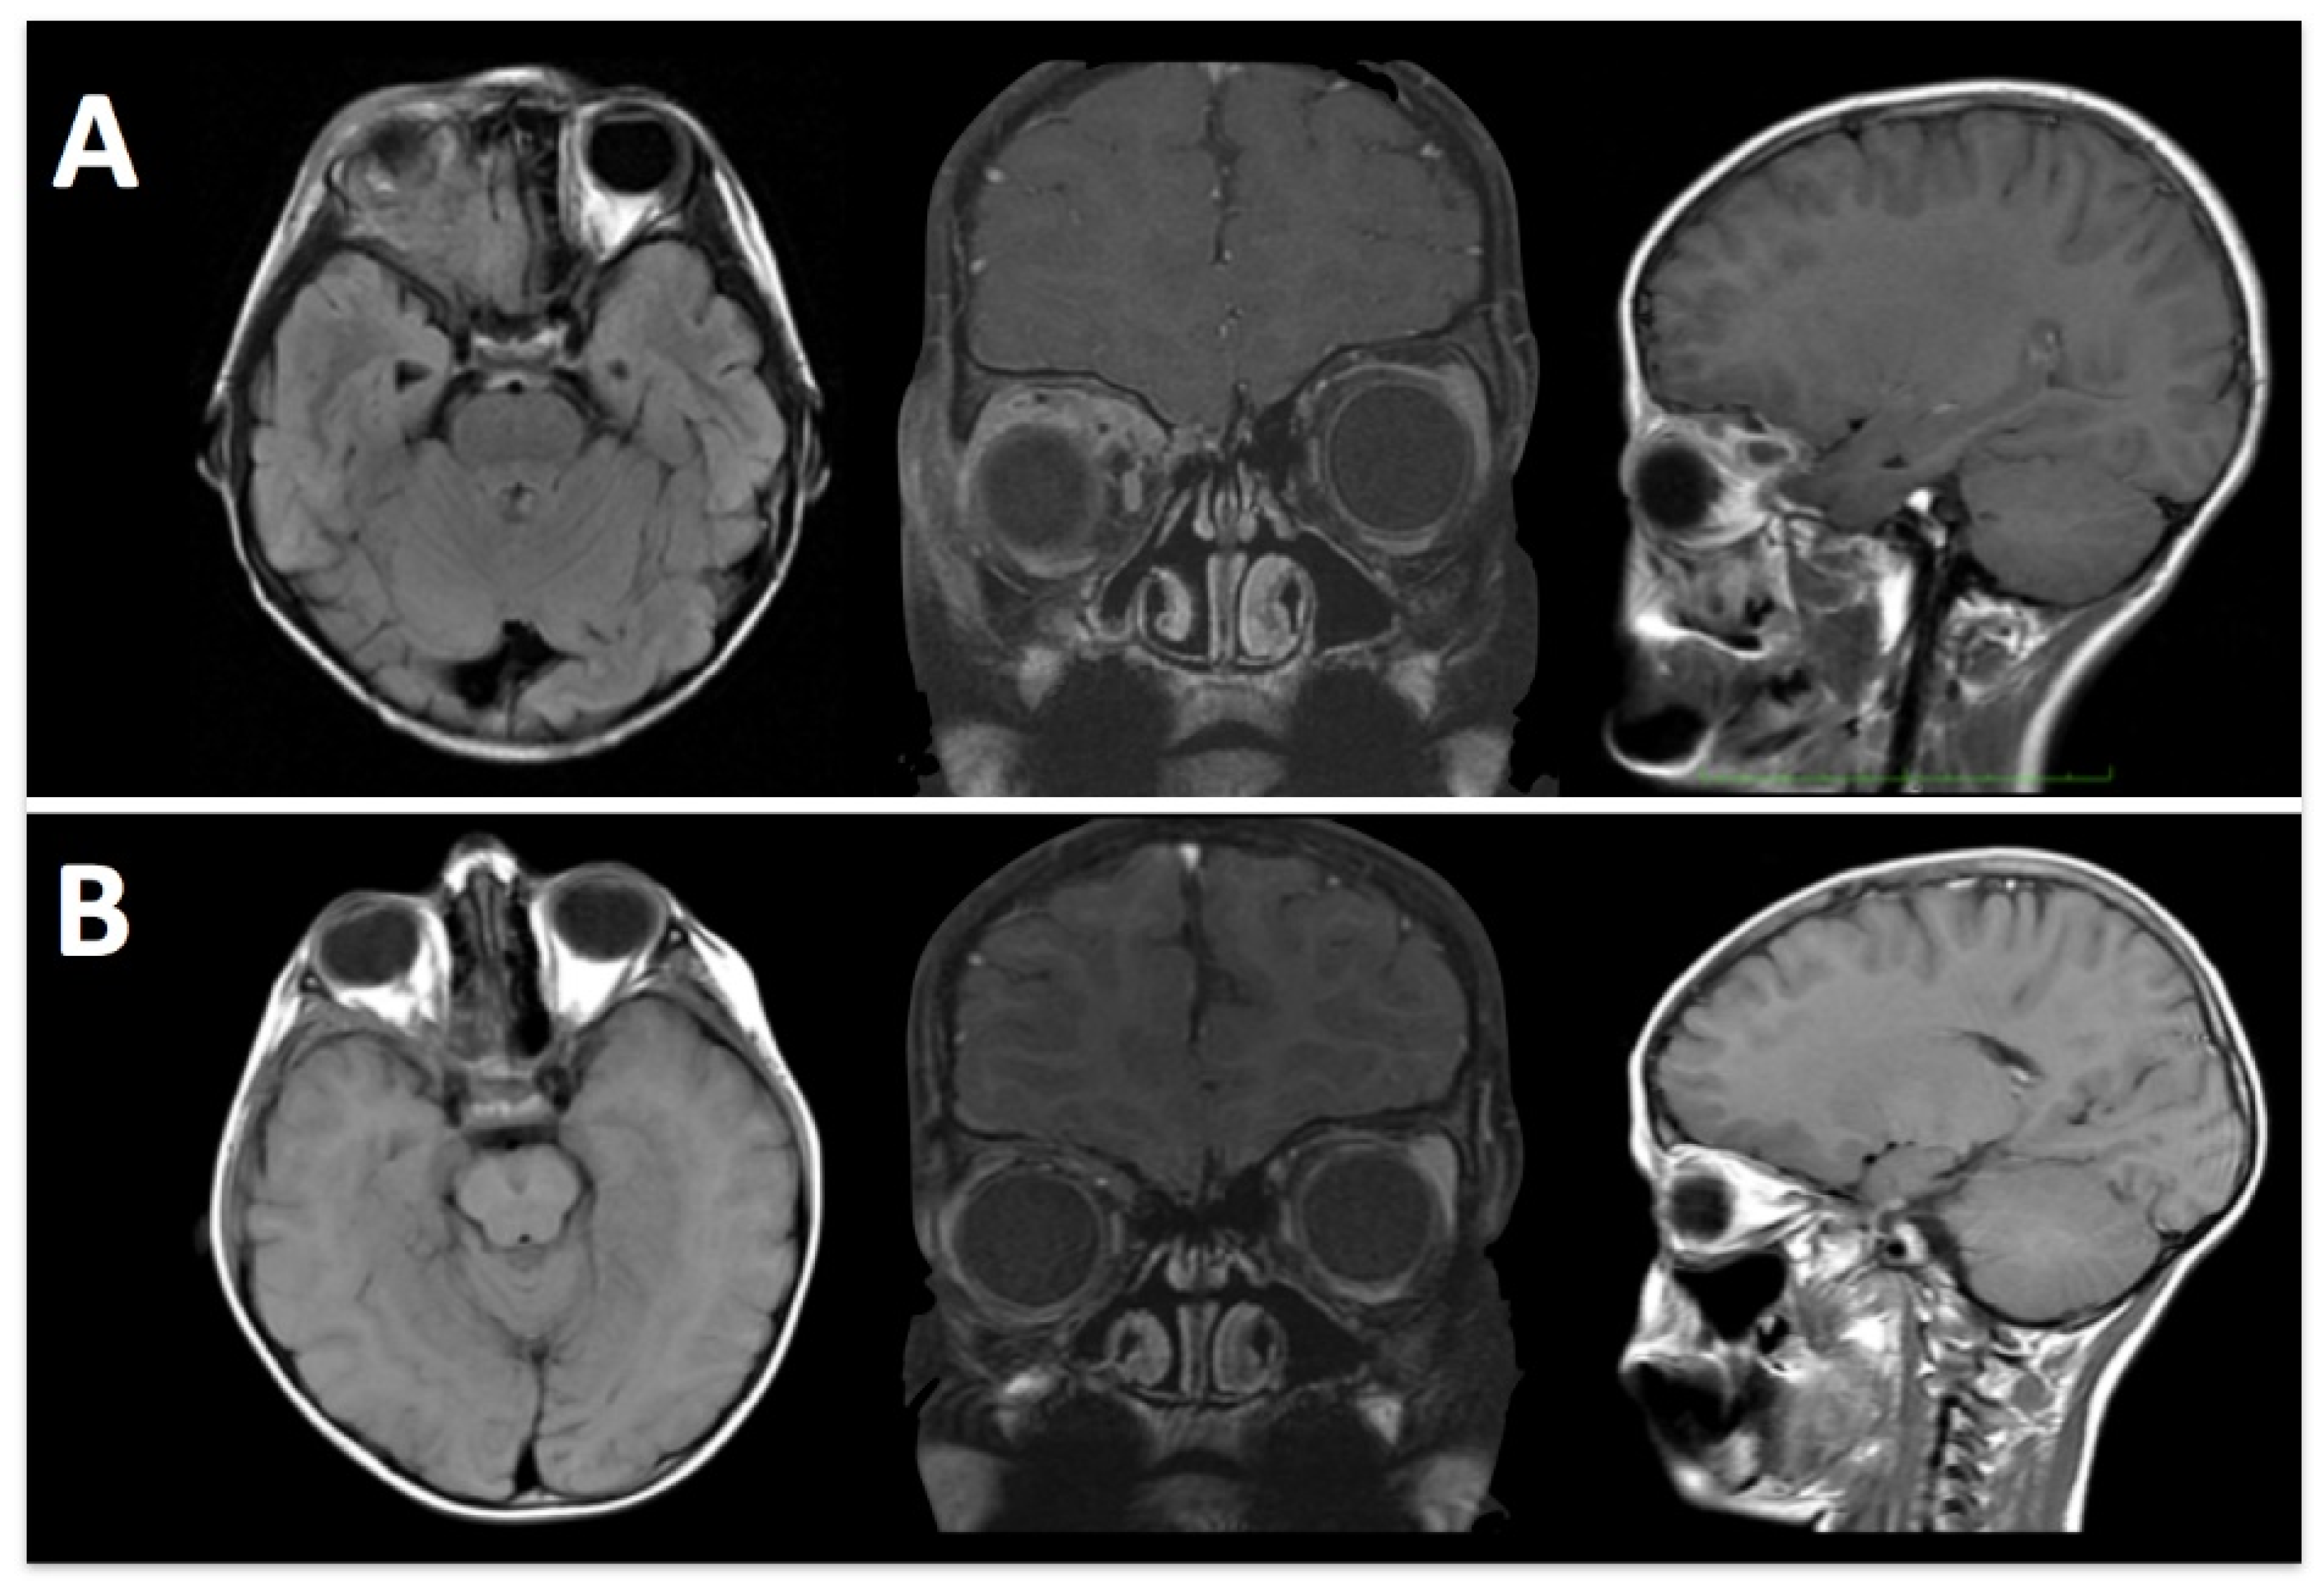

In this study, the extended sphenoid ridge approach (E-SRA) provided comparable exposure with other skull base approaches, while minimizing the need for extensive soft tissue dissection (Figure 4).

Figure 4. A 12-year-old girl admitted with diabetes insipidus and a growth delay. (A) Pre-operative MRI shows a sellar mass with extension to the infundibular stalk. (B) Postoperative MRI shows a gross-total resection.